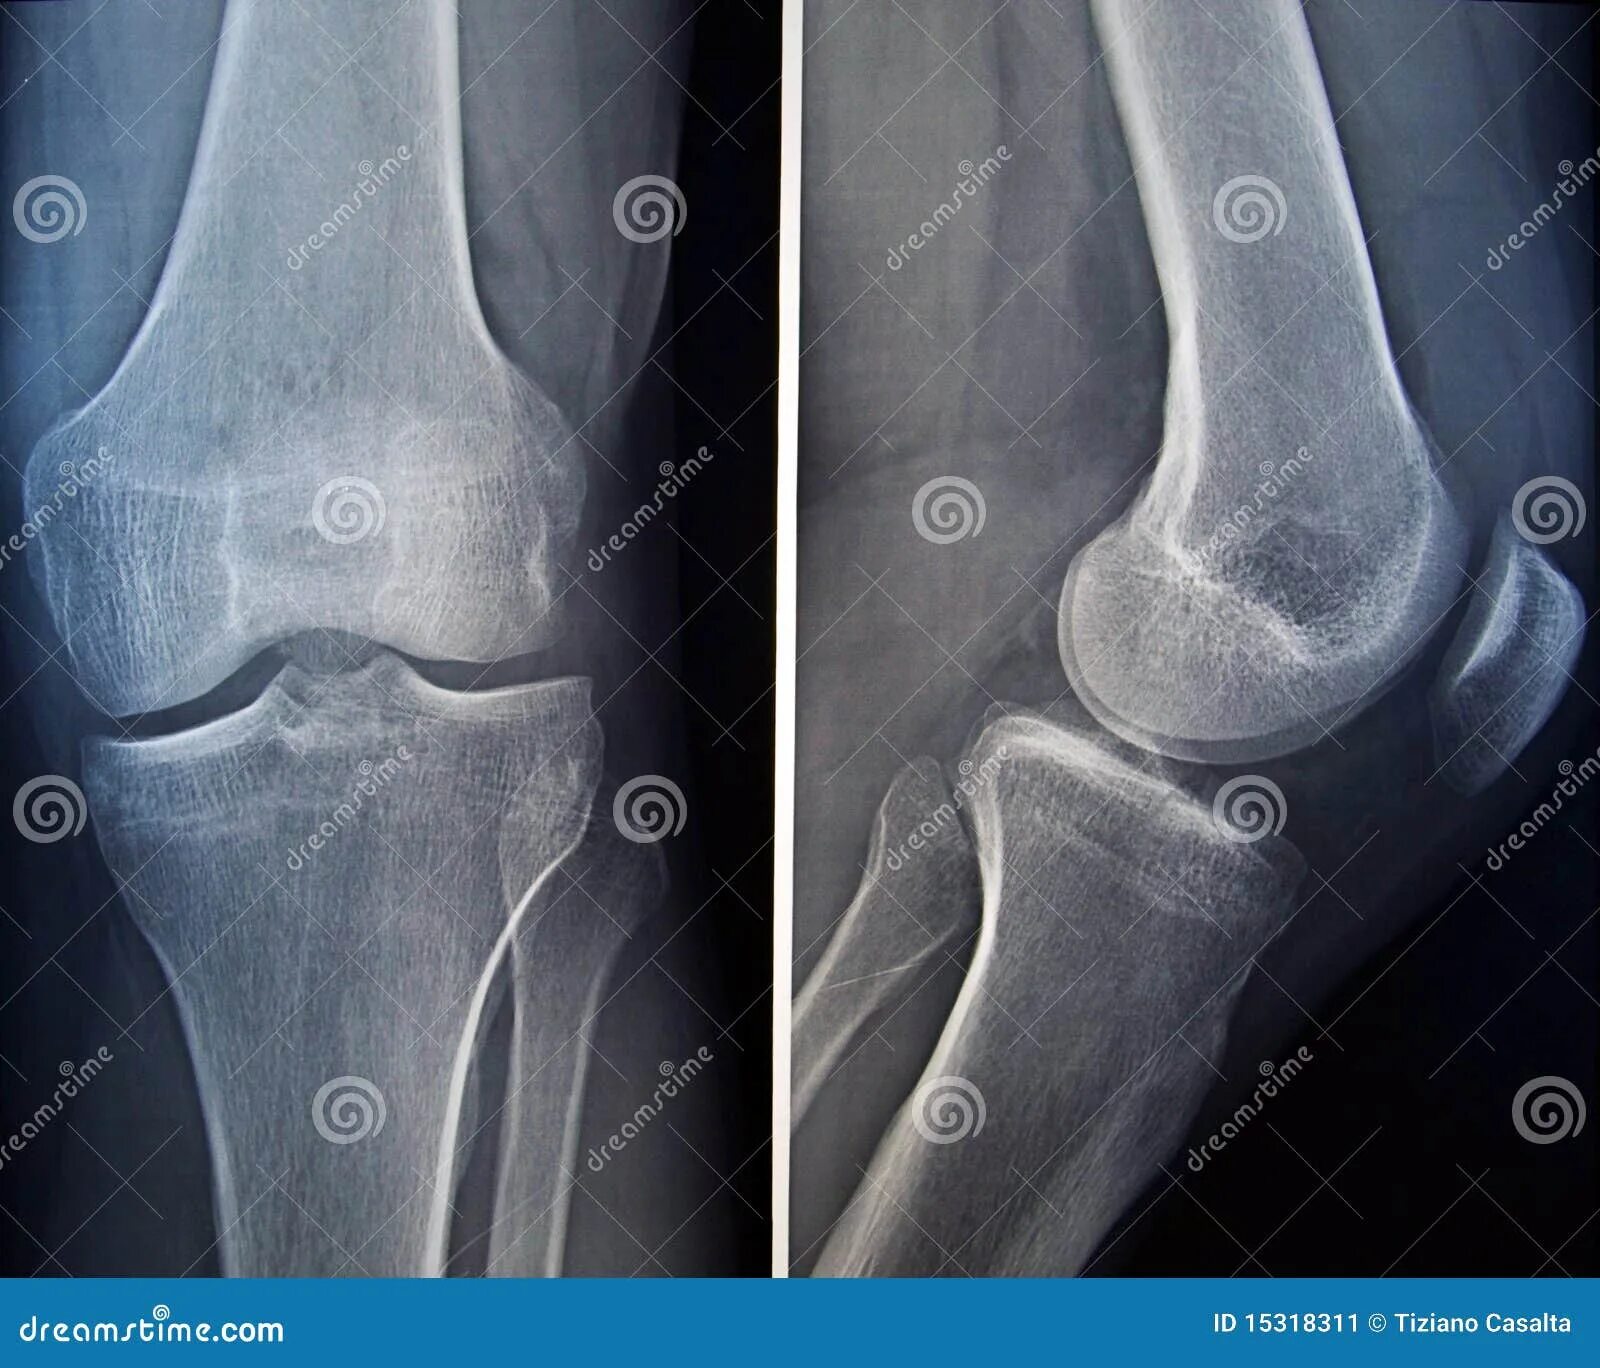

Рентгенография коленного сустава 2 проекции